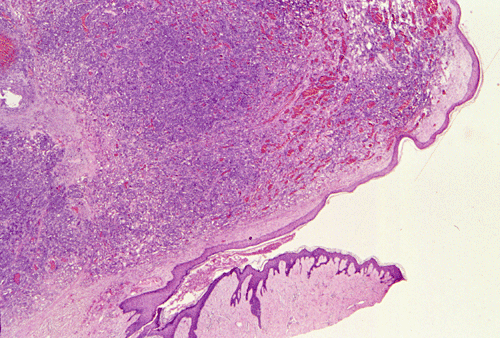

Panel A, B and F are taken from the dermal-epidermal junction. Panel B, C, D, and E are taken from the same area. Panel F, G, H, and I are taken from the same area

The tumor appears to be centered on the dermis and does not involve breast parenchyma in the sections examined A (not shown). On low-magnification (Panel A, B and F), the lesional tissue is a highly cellular and vascular tumor in the dermis. The large areas of hemorrhage ("blood-lake") and dilated vascular channels (Panel A, and F) probably correspond to the "red nodules and yellow patches" on physical examination. Although the tumor extends deeply into the subcutaneous tissue (not shown here), there is no evidence of invasion in to the epidermal layer (Panel A, B and F). The histology of this tumor varies in different areas. In some areas, it appears as a densely packed spindle cell tumor with exuberant and irregular and anastomosing vascular channels (Panel B, C, and D). The endothelial cells protrudes into the vascular channels and had enlarged, hyperchromatic nuclei with  prominent nucleli. In another area, the lesion contains numerous ectactic and anastomosing vascular channels (Panel F, G, H, and I). Pleomorphic changes are also prominent in the vascular cells in these areas. On immunohistochemistry, the tumor cells are immunoreactive for CD31, CD34 (not shown).